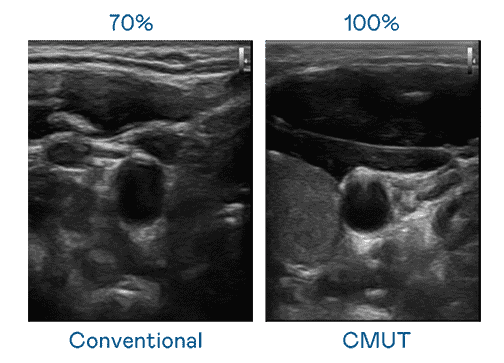

CMUT 技术是一种用电容式微机电元件来产生超音波讯号的技术。。与传统 PZT 压电式技术相比,,,,CMUT 频宽增加 30%,,,,更宽频的超音波讯号让影像解析度大幅提升,,是实现高影像品质医疗超音波扫描、、、促进精准医疗发展的关键技术。。。。

大频宽带来超清晰影像

超音波影像的解析度高低,,,,首先取决于探头能发出的讯号频宽。。。牛牛游戏 CMUT 可提供高清晰的超音波讯号,,,,提供高频宽、、、、高灵敏度、、、、影像纹理细节更高的超音波影像,,协助医护人员缩短影像判读时间及利用精准的医疗影像进行诊断。。。